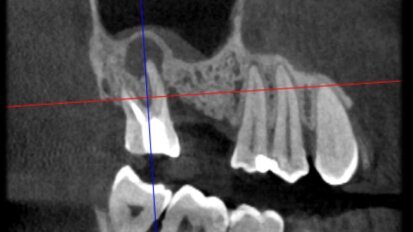

Atraumatic extraction of maxillary first premolar

A 70-year-old female patient visited our clinic owing to a fractured maxillary first molar. Tooth #24 had previously had a large composite restoration that ...